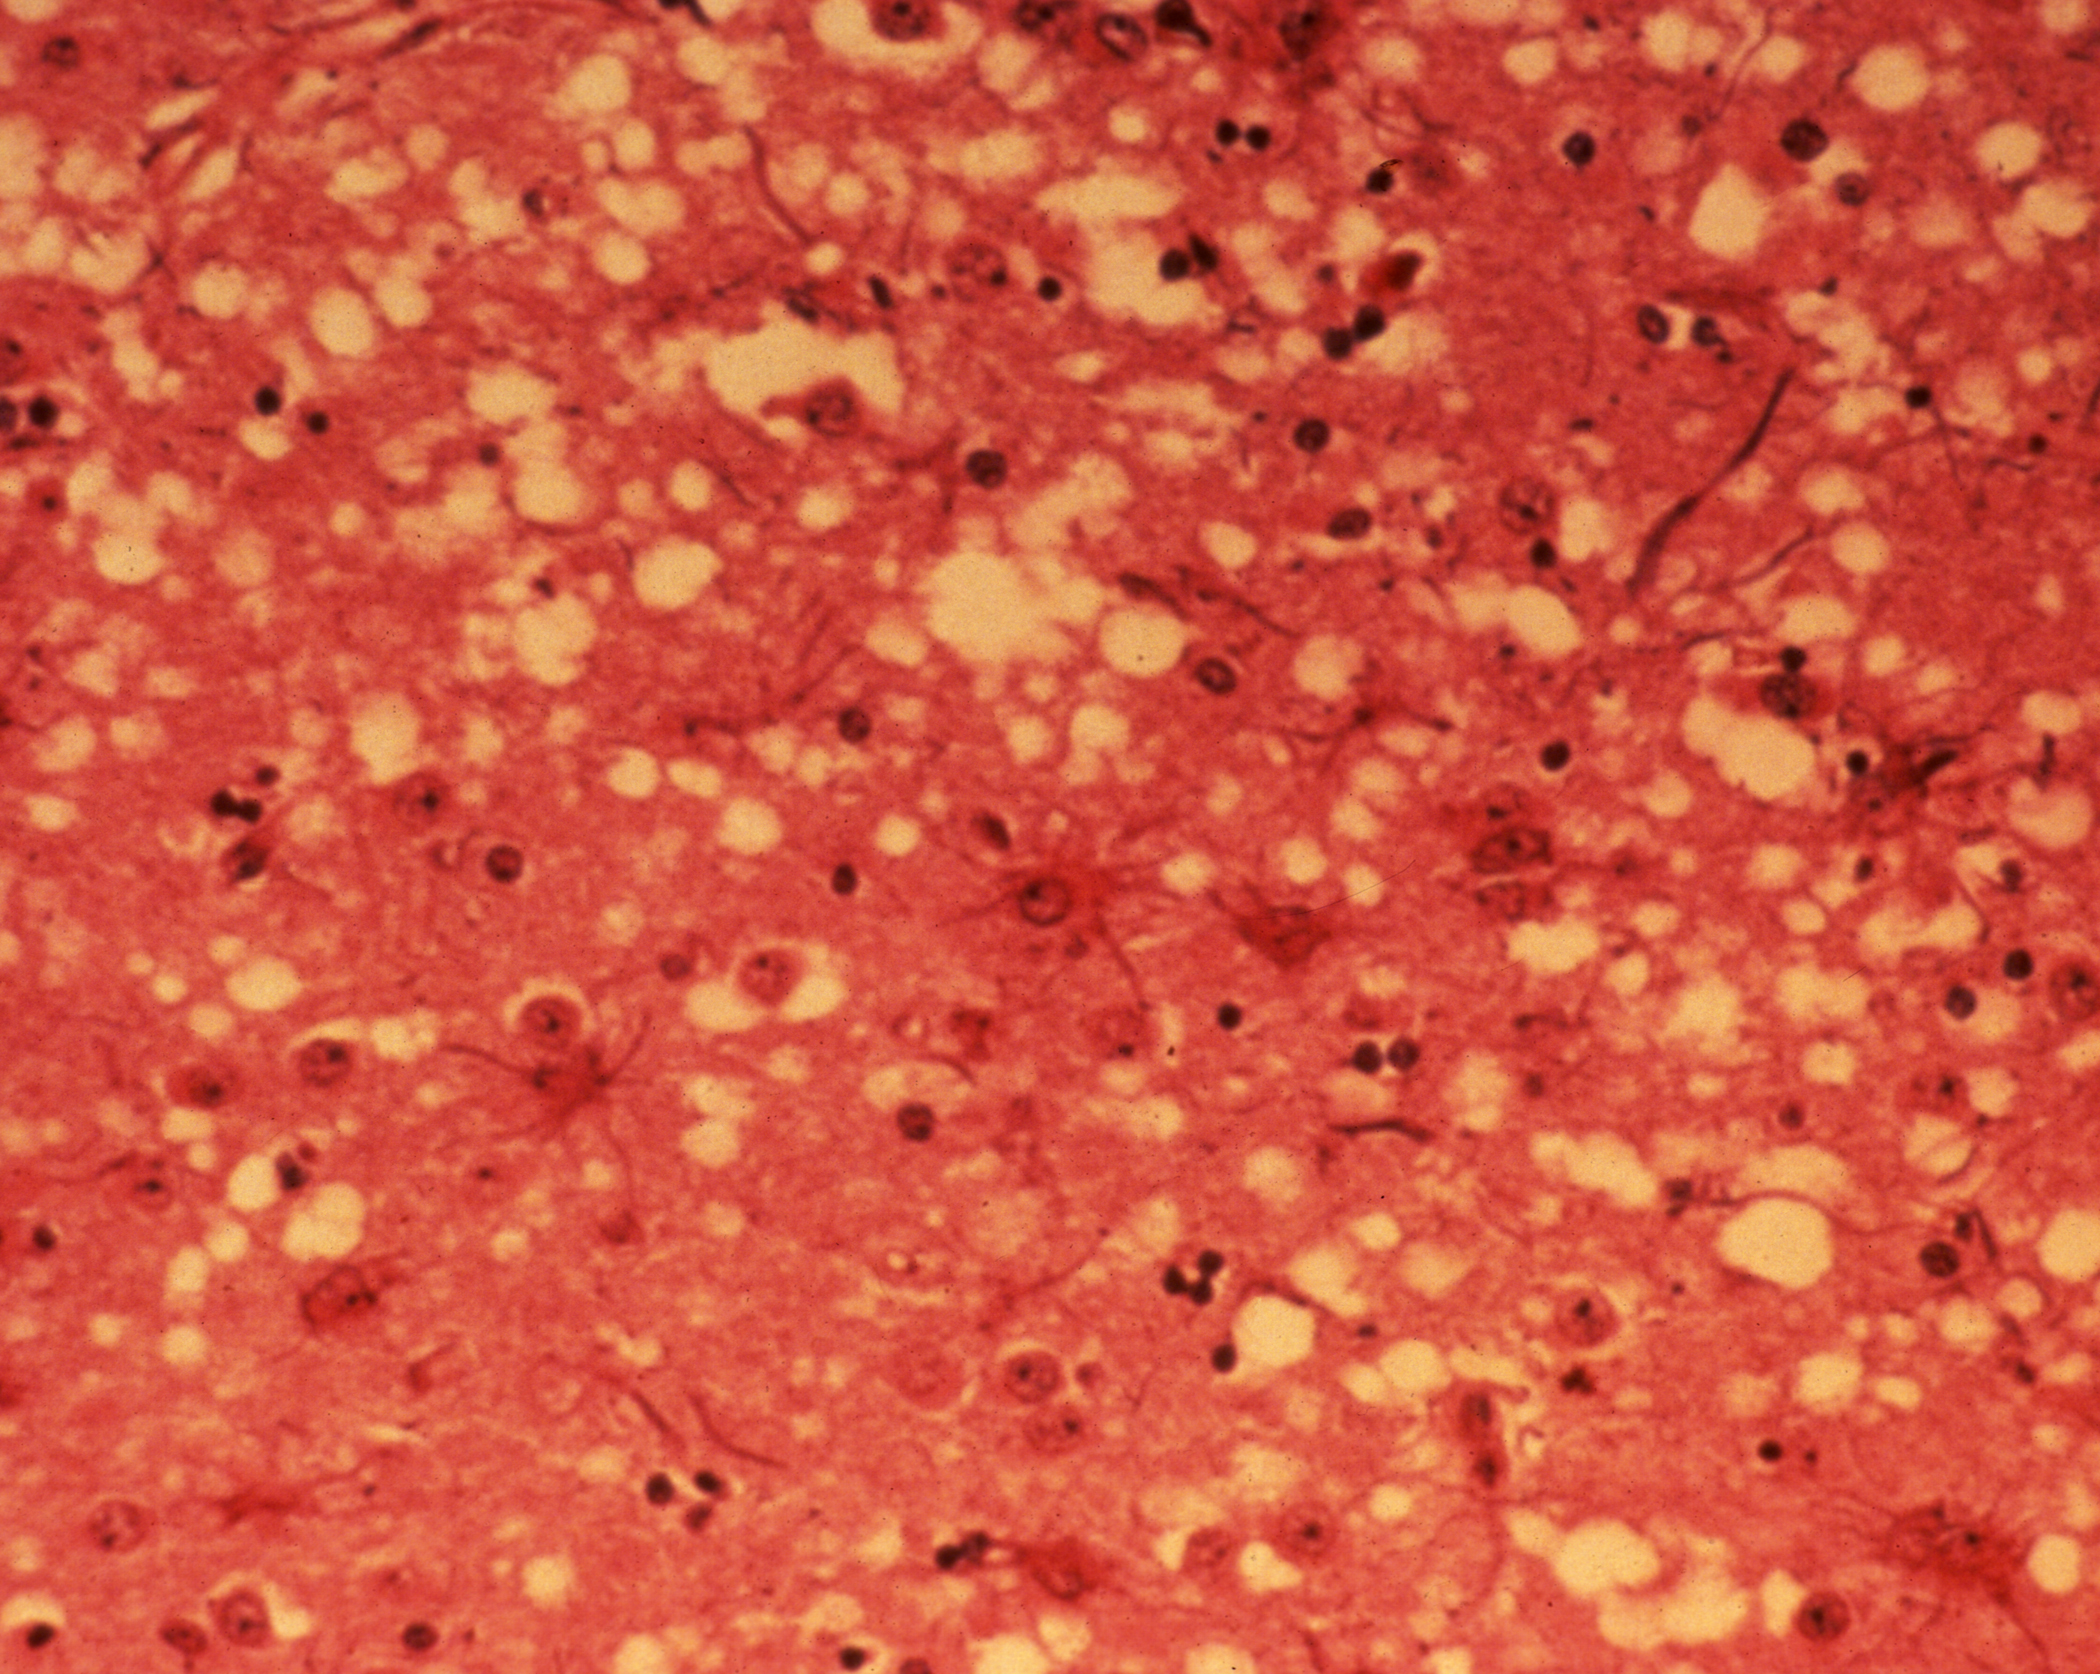

변형 프리온(PrPSc)이 체내에 유입되면, 뇌에 존재하는 정상 프리온 단백질(PrPC)을 점진적으로 변형시킨다. 변형된 프리온은 다시 다른 정상 프리온을 연쇄적으로 변형시켜 그 수가 기하급수적으로 증가하게 된다. 이렇게 증가한 변형 프리온들은 서로 뭉쳐 아밀로이드 플라크라는 단백질 덩어리를 형성하고, 이는 뇌 신경세포를 파괴하여 뇌 조직에 스펀지처럼 미세한 구멍이 뚫리는 해면상 변화를 일으킨다. 이로 인해 소는 신경계 이상 증상을 보이다가 결국 폐사한다.[15] 감염된 소는 2년에서 8년 정도의 긴 잠복기를 거친 후 증상을 나타내는 것으로 추정된다.[123][124]

현재, 신경병리학적 및 면역조직화학적 방법을 사용하여 ''사후'' 뇌 조직을 검사하는 것 외에는 변형 프리온 단백질(PrPSc)을 신뢰성 있게 감지할 수 있는 방법이 없다. 비정상적으로 접힌 PrPSc 형태의 PrP 축적은 질병의 특징이지만, 혈액이나 소변과 같이 쉽게 접근할 수 있는 체액에서는 매우 낮은 수준으로 존재한다. 연구자들은 PrPSc를 측정하는 방법을 개발하려고 시도했지만, 혈액과 같은 물질에 사용할 수 있는 방법은 아직 완전히 받아들여지지 않았다. 전통적인 진단 방법은 뇌의 숨뇌 및 기타 조직에 대한 ''사후'' 조직병리학적 검사에 의존하며, 면역조직화학은 프리온 단백질 축적을 입증하는 데 사용될 수 있다.[25]